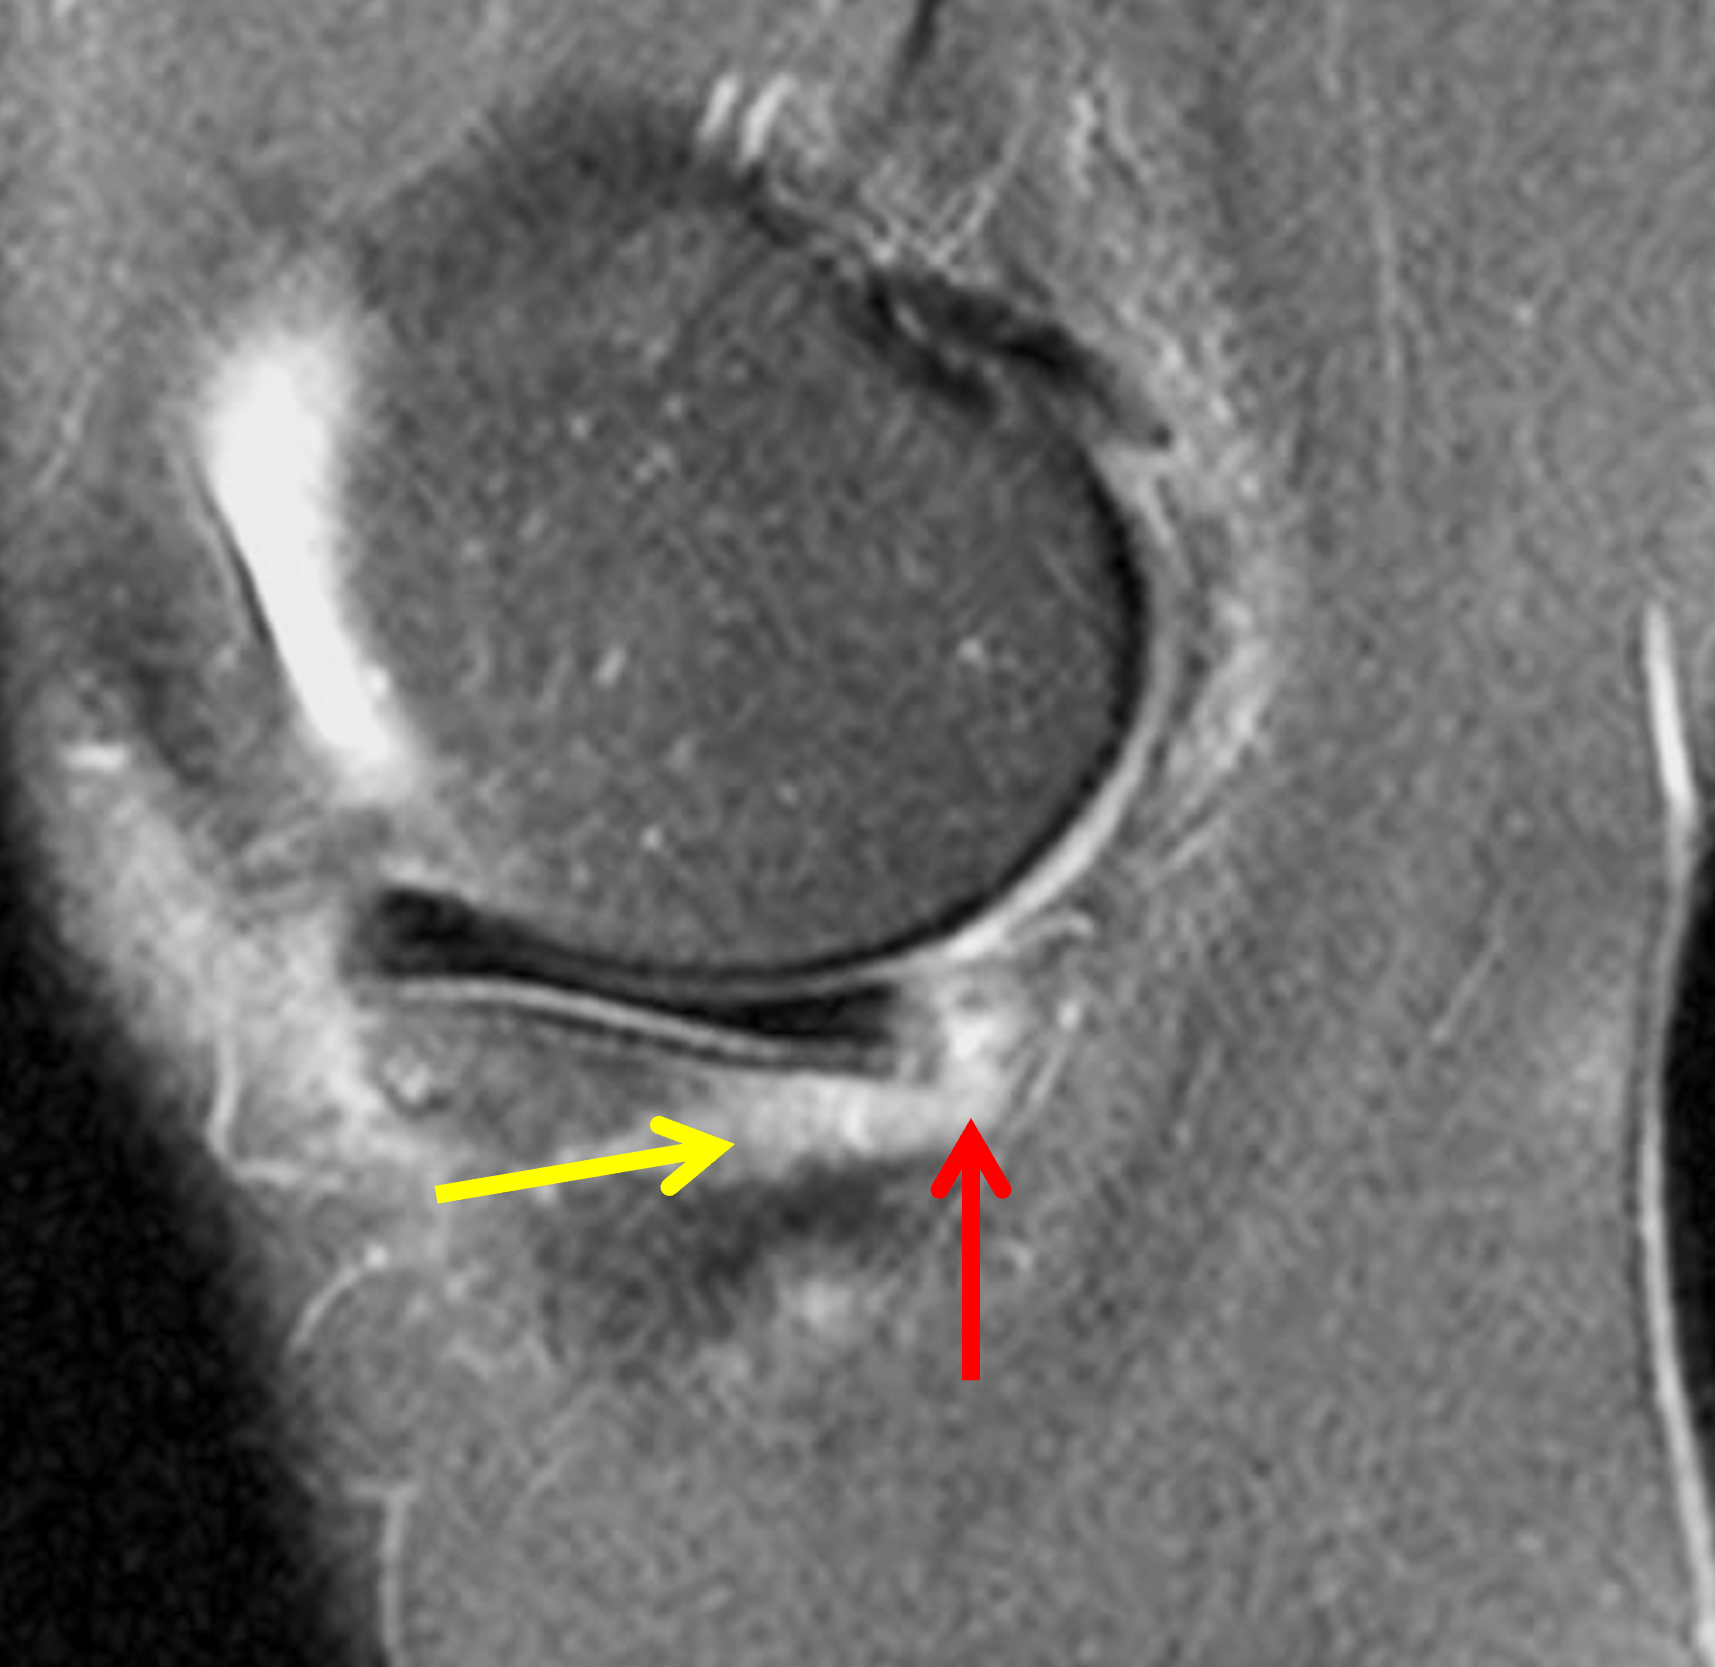

A 19-year-old collegiate baseball player sustained a twisting injury to the knee 3 weeks earlier. Sagittal (1A) proton density-weighted fat-suppressed image through the intercondylar notch, (1B and 1C) proton density-weighted images through the medial compartment, and (1D) fat-suppressed proton density image through the medial compartment are provided. What are the findings? What is your diagnosis?

Figure 2: (2A) Sagittal image through the intercondylar notch shows a complete tear of the anterior cruciate ligament (arrowheads). (2B and 2C) Near the posterior meniscocapsular junction of the medial meniscus, there is disruption of the posterior meniscotibial ligament (red arrow) and irregularity of the posterior meniscocapsular ligament (yellow arrow). (2D) On the fluid-sensitive sequence, linear high signal intensity is interposed between the ligaments and the posterior horn of the medial meniscus (arrowheads).

Anterior cruciate ligament tear with a medial meniscal ramp lesion.